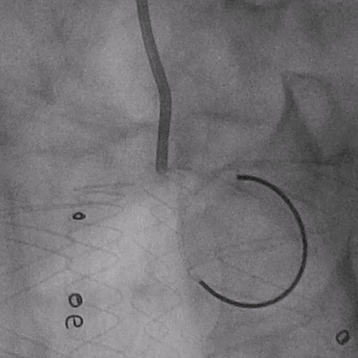

02. 沿左肱动脉穿刺并引入标记导管于升主动脉造影,见左椎动脉优势明显,LSA与LCCA距离小于10mm。

03. 控制性降压至90/55mmHg左右,沿右股动脉入路引入超硬导丝及华脉泰科胸主支架PTBS3430180,术中沿LCCA后缘处缓慢释放1-2节,再次造影确认定位精准后继续释放主体支架,造影示覆膜支架未覆盖LCCA,覆盖LSA。

04. 沿左肱动脉引入5F Ver导管,头端垂直抵住主体支架覆膜,引入0.035″长泥鳅导丝配合导管顺利破膜,进入主动脉。